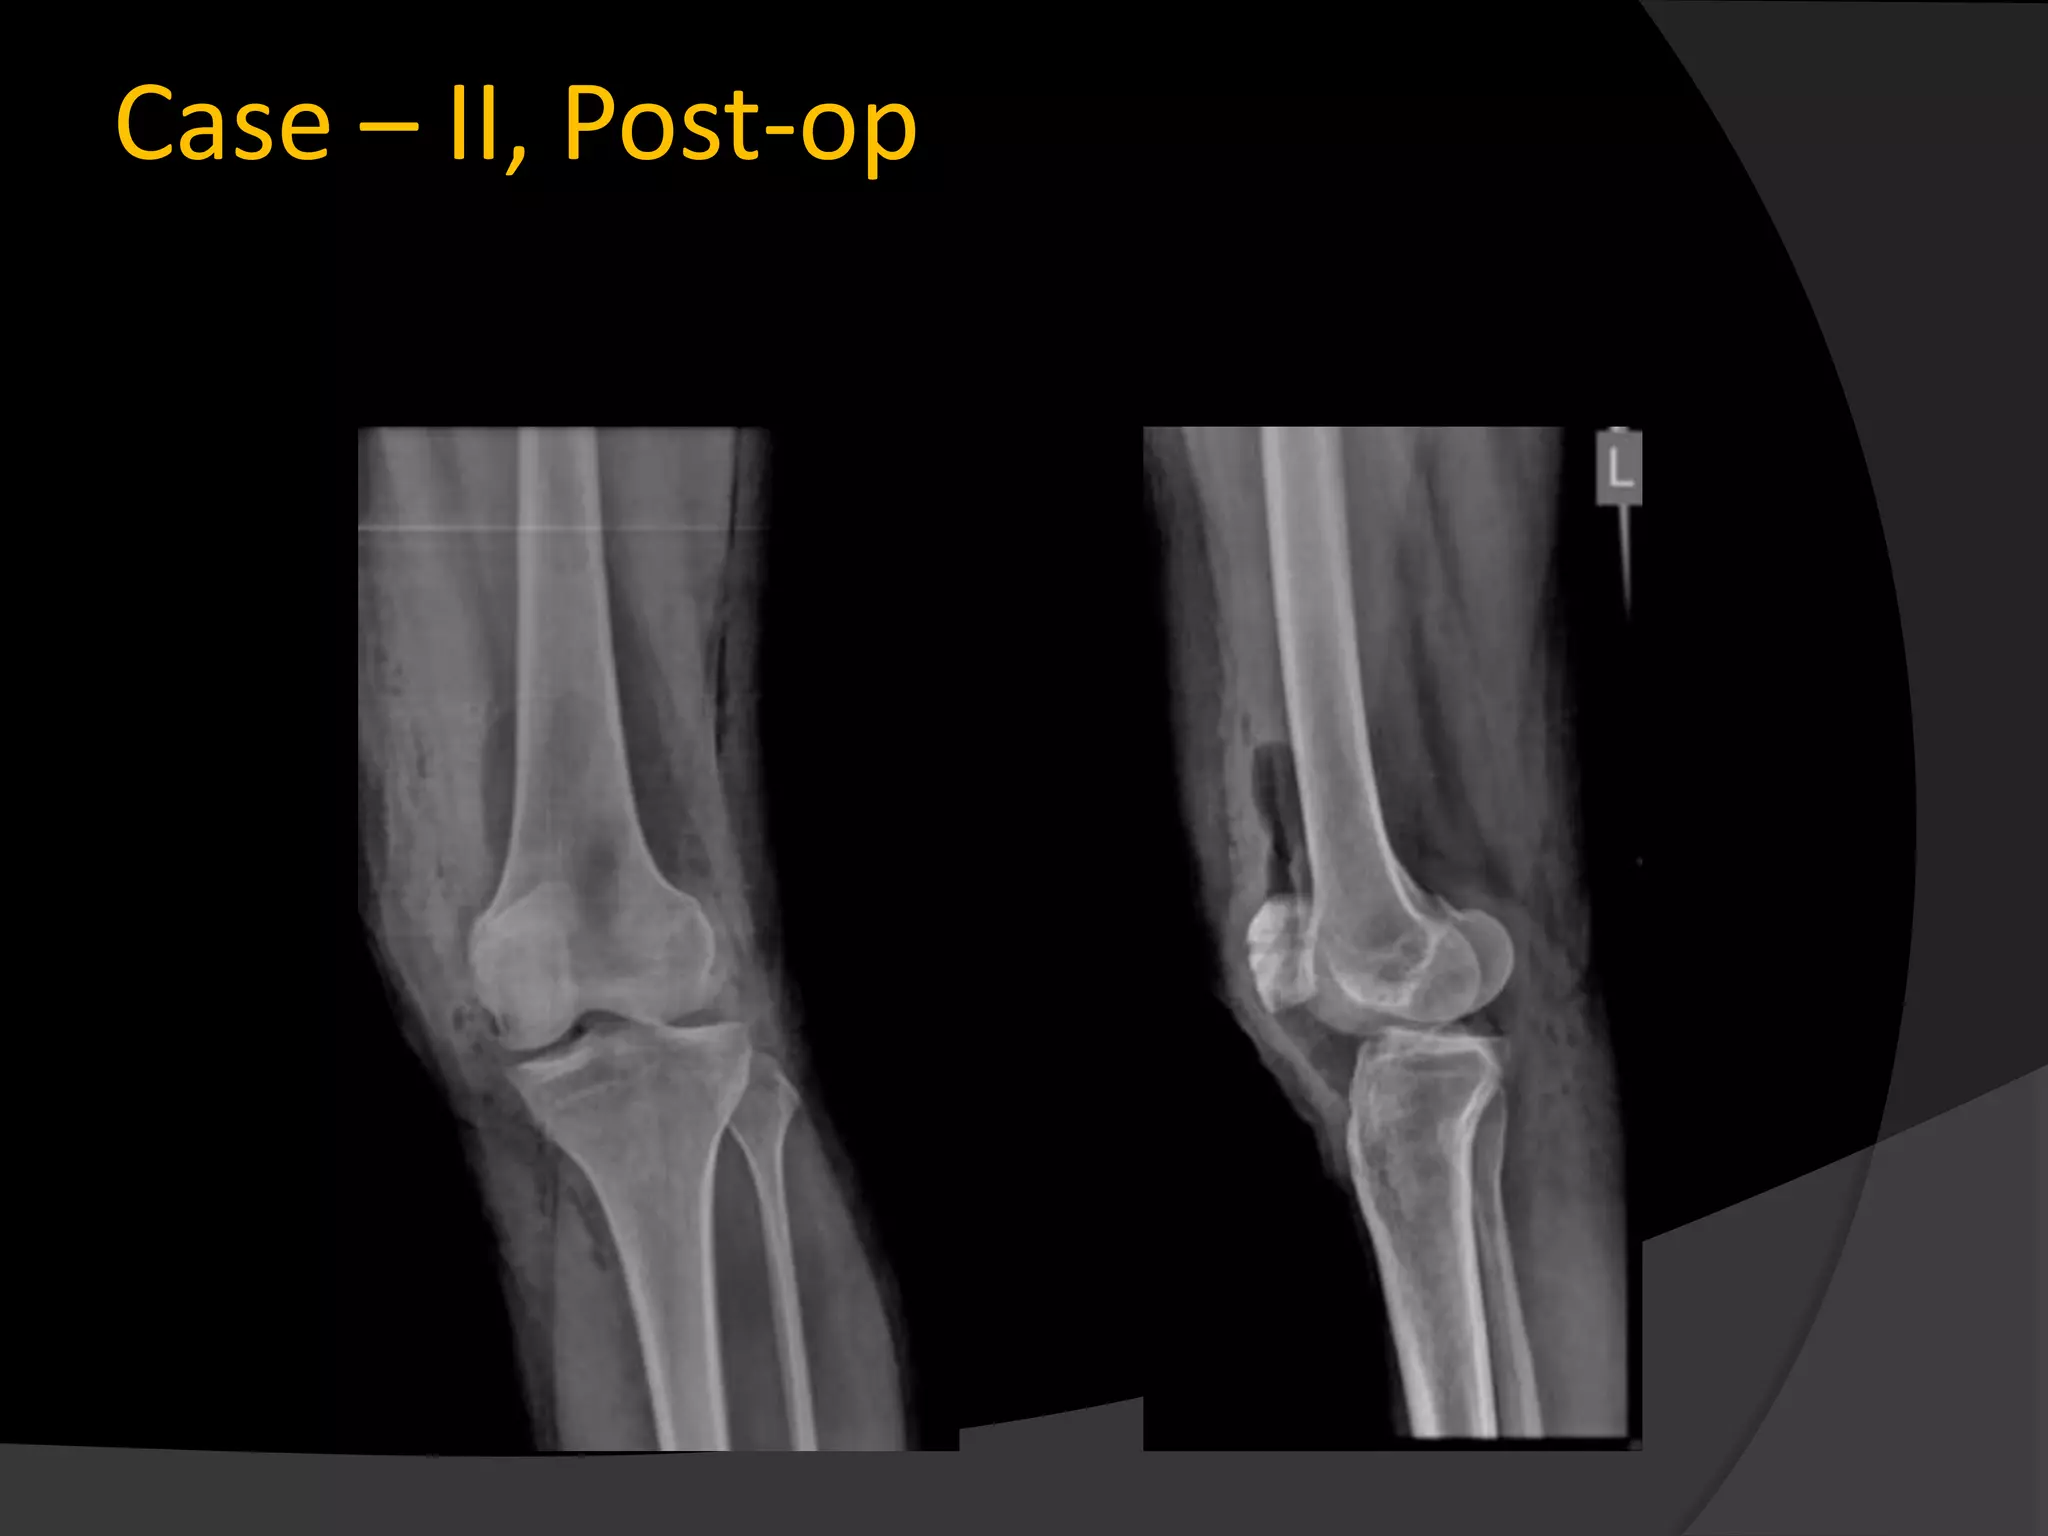

Case – II, Post-op

Case – II,Post-op